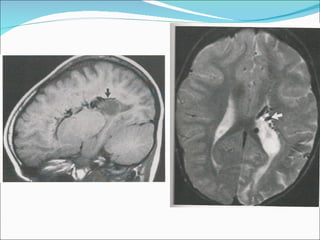

1) O documento descreve o Síndrome de Sturge-Weber, uma condição neurocutânea não hereditária caracterizada por nevo facial e convulsões. 2) O Angioma Cutâneo de Sturge-Weber aparece na área de inervação do trigêmeo, enquanto o Angioma Leptomeningeal aparece nos sulcos corticais parietais e occipitais. 3) Os achados de imagem incluem realce no espaço subaracnóideo e hipersinal na substância branca adjac